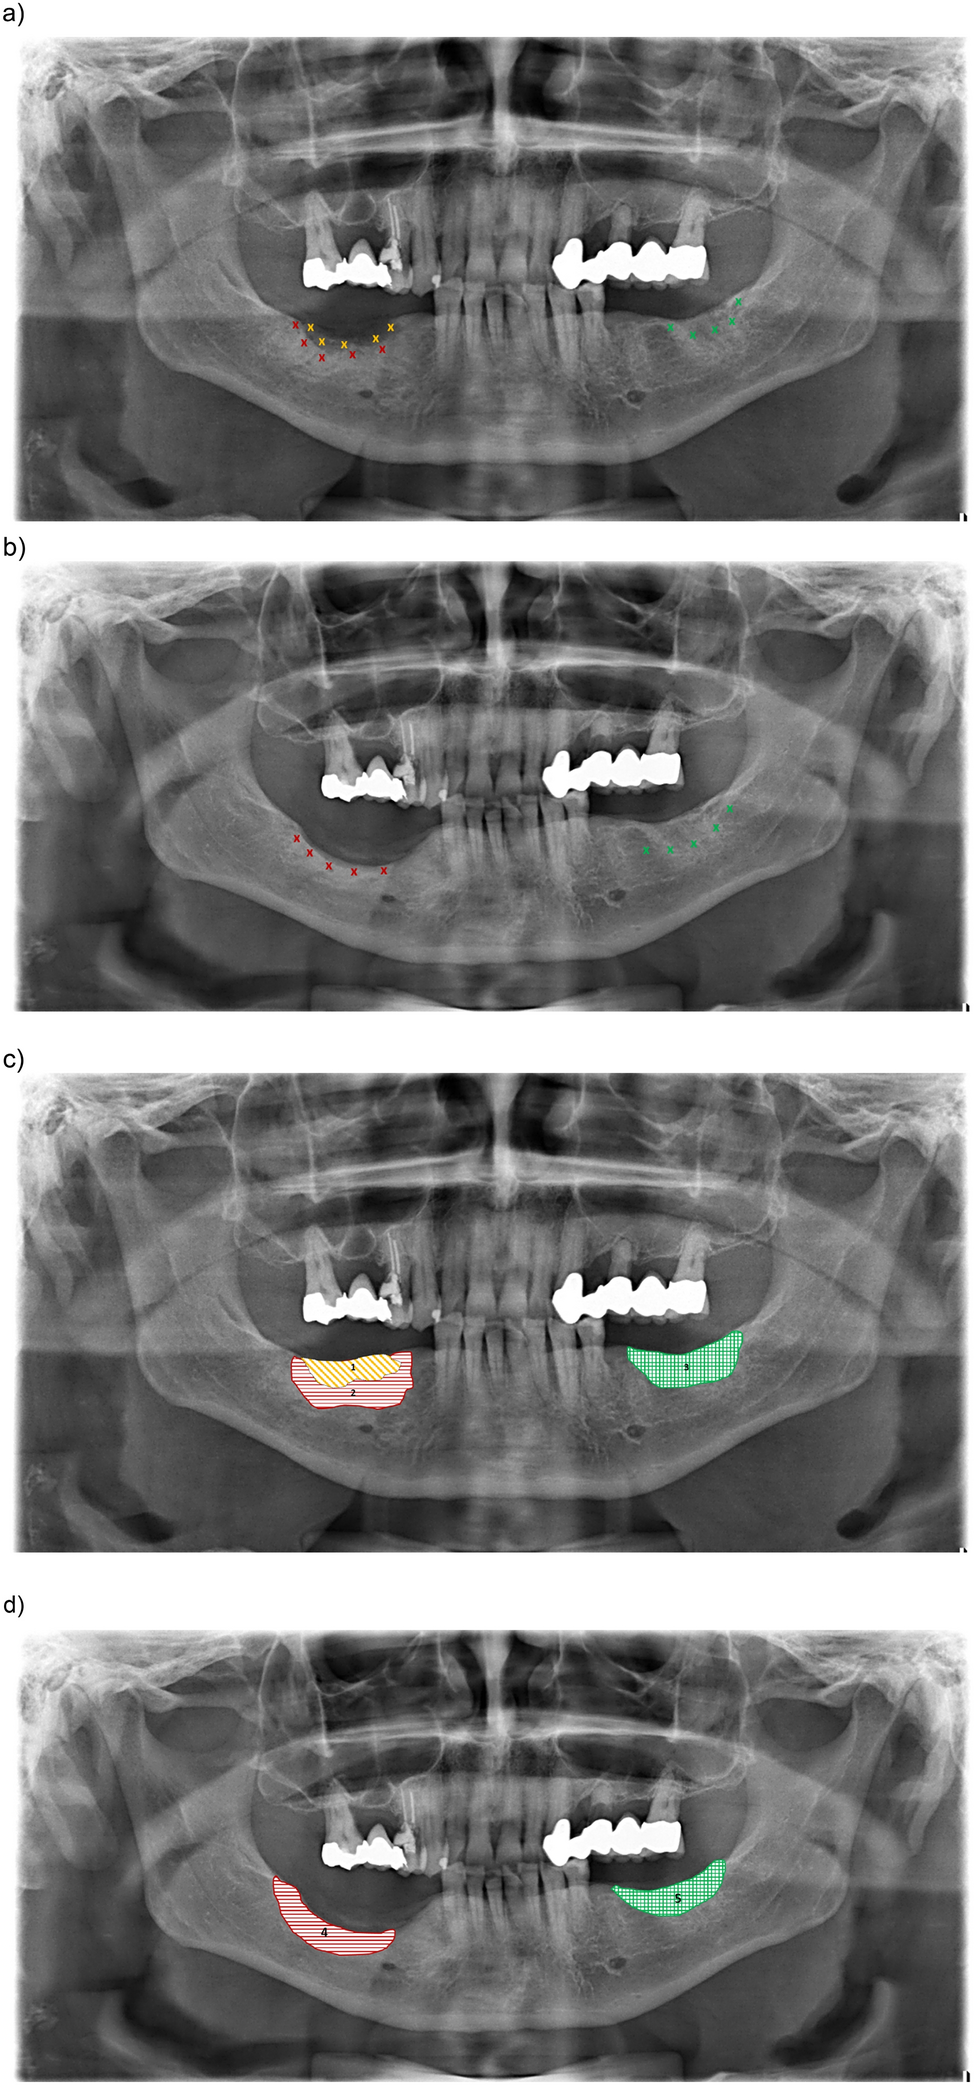

Figure 2

Pre and postoperative panoramic radiograph (a,b) measuring points (Sidexis), (c,d) measured bone zones (ImageJ): 1: osteonecrosis; 2: preoperative sclerotic area; 3: preoperative unaffected reference side; 4: postoperative reactive sclerotic area; 5: postoperative unaffected reference side.